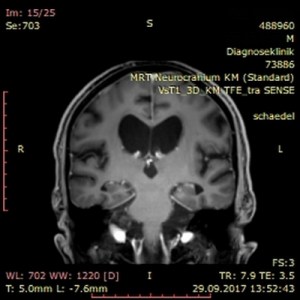

Dieser Tage erhielt ich einen erschreckenden Einblick in das Ausmaß der Zerstörung Meinerselbst durch Vater und Mutter, die beiden Mörder meiner Seele. Auf der diagnostischen Suche nach der Ursache für meinen Schwankschwindel wurde auch mein Schädel fixiert und per MRT durchleuchtet. Nach der 25minütigen Prozedur in der Röhre traf ich den Radiologen vor dem Bildschirm und sah mir scheibchenweise ins Gehirn. Der Arzt war sichtlich betroffen über die auffällige Atrophie meines Gehirns. Er zeigte mir die ungewöhnlich ausgedehnten Ventrikel, sprich Hohlräume, an den Seiten und im Innenraum meines Brägens. Er fragte nach möglichen Erkrankungen wie Diabetes und Bluthochdruck. Ich verneinte und erwähnte meine PTBS. Er erkundigte sich nach der Ursache, ich verstand die Frage akustisch nicht, meine Frau antwortete für mich: sexueller Missbrauch und Misshandlung durch die Eltern. Nun kam zu seiner Betroffenheit noch ein tieftrauriger Zug, und er erklärte mir, dass Missbrauch und Misshandlung derlei tiefe und bleibende Spuren im Gehirn hinterlassen. Angesichts meiner geistigen Präsenz zeigte er zudem über die strukturelle Regenerationsfähigkeit des Gehirns Erstaunen. – Später sah ich im Internet das „Schalenhirn“ eines Mathematikers mit einem IQ von 126, das nur geschätzte 100 g Masse besaß (siehe hier).

In meinem Therapietagebuch notierte ich dazu trocken: „Neben dieser Diagnose: keine Blutungen, keine Aneurysmata, keine Tumore oder Metastasen. Nur ein weiterer Ausschluss auf der Diagnose zum psychogenen Schwankschwindel. Die Hirnatrophie selbst ist nur ein Sachverhalt des Missbrauchs, man kann auch mit einem „Resthirn“ gescheit und sinnenfroh überleben.“

Als Hörbeispiel meiner nachhaltigen Schädigung von Angst und PTBS habe ich abschließend ein Video des Bordun Orchesters eingebettet. Die Bilder in diesem Beitrag kehren mein sichtbar zerstörtes Inneres, sprich mein Gehirn, nach außen.

kurz zu ihren schnittaufnahmen vom kopf. ich bin kein fachmann und kann damit nicht viel anfangen, obwohl ich vor vielen jahre einem oberarzt erklären musste, wir er mit schnittaufnahmen umzugehen hat. er sagte über die aufnahmen unseres jüngsten den ermutigenden satz: aber der hat ja kein gehirn. – ich habs ihm dann gezeigt. unser jüngstes kind, ein adoptivkind, kam mit einem hirnschaden zur welt, dazu gehörte der hydrozephalus (wasserkopf). ganz beiläufig hatte ich im psychologie-studium gelernt, dass man auch mit hydrozephalus beachtliche leistungen erbringen kann.